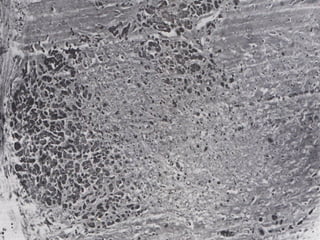

• #30 Hypertrophic cardiomyopathy is the single most common cause of sudden death in adolescent and young adults. It shows an autosomal dominant genetic inheritance. On gross, the left ventricle is hypertrophied without dilatation. The hypertrophy is disproportionate, asymmetrical in the septum as compared to the left ventricle. This causes obstruction to the outflow tract. Rarely, it may also present as concentric hypertrophy of the left ventricle similar to that seen in hypertensive patients. On microscopy, the myocardial fibers are in dissary with presence of bypertrophied bizarre myocardial cell. This is typically seen in the septal myocardium.

• #31 This is a microscopic view of the myocardium seen under 160 x magnification that shows groups of myocardial fibers that are arrange haphazardly as well as replacement of some myocardial fibres by connective tissue.

• #32 This is a microscopic section of the myocardium showing a cross-section of a small branch of the coronary arteries seen under 160 x magnification. The artery is seen to have thick walls and reduced luminal cross-sectional area. Presumably the arterial wall changes are secondary to the myocardial disease.

• #33 This is a microscopic view of a cut section of the heart seen at 160 x magnification. This shows the bizarre arrangement of clusters of myocardial fibers as seen in hypertrophic cardiomyopathy. This section is from a 7 year old girl who died suddenly and unexpectedly.